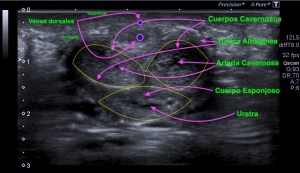

333.Revisión patología testicular. El Varicocele. Tipos y Clasificación.

Son venas del plexo pampiforme de aspecto tortuoso y dilatadas por encima de los 2 mm.

El Varicocele es primario o idiopático debido a una alteración de la vena espermática y su drenaje por mal funcionamiento de las válvulas testiculares.

Es más frecuente que el secundario debido a que la vena testicular izquierda es más larga que la derecha cuyo trazo es más corto y hace drenaje directo en la VCI.

El Varicolece Secundario se debe a aumento de presión por figuras patológicas como hidronefrosis, cirrosis o compresiones de la vena renal izquierda o neoplasias.

Varicolece. Maniobra de Valsalva.

Medida superior a 2 mm. Grado 1.

Clasificación basado en el diámetro venoso del plexo pampiniforme (en reposo):

Grado 1: Entre 2,5 y 4 mm

Grado 2: Entre 4 y 5 mm

Grado 3: Mas de 5 mm

Estas medidas son de una de las clasificaciones que se usan para el estudio del varicocele. Hay alguna otra de la que hablaremos más adelante, pero esta me parece sencilla para comprender esta habitual figura patológica.

Estas medidas son en reposo y aumentan con la maniobra de valsalva. Ojo.

Existe aumento de flujo con la maniobra de Valsalva como puedes ver en el vídeo.